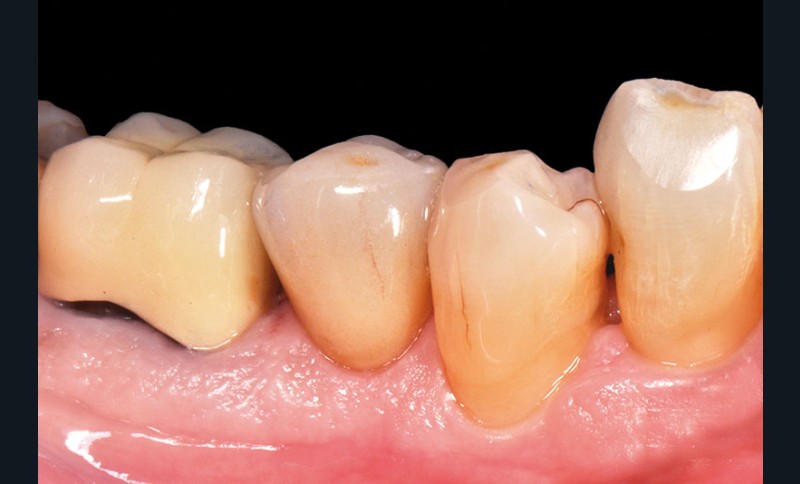

Un patient de 61 ans se présente en consultation pour un contrôle de routine. L’examen endobuccal montre une volumineuse restauration en composite en distal de 45.